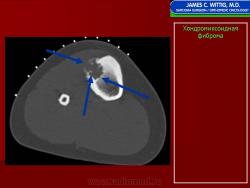

Рентгенологическое исследование показывает, что опухоль растет экзофитно в зоне метафиза и распространяется по направлению к эпифизу. Она имеет четкие и фестончатые очертания. На фоне характерных литических изменений изредка видны участки обызвествления. Наиболее агрессивный вид имеет хондромиксоидная фиброма, локализующаяся в позвонках. Здесь часто отмечается прорастание надкостницы. Макроскопически представляет собой четко отграниченную опухоль, имеющую дольчатое строение, плотную консистенцию, серовато-белый или синюшно-серый цвет. При прорастании новообразования через кортикальный слой надкостница сохраняется. В редких случаях наблюдается имплантация опухолевой ткани в окружающие мягкие ткани. Для лечения хондромиксоидной фибромы используется кюретаж. Рецидивы наблюдаются в 10—15 % случаев, обычно в течение первых 2 лет после операции, чаще всего у лиц моложе 15 лет.

Рентгенологическая картина. Хондромиксоидная фиброма длинных трубчатых костей в типичных случаях представлена метафизарным или метадиафизарным, эксцентричным, четко очерченным, овальным очагом разряжения костной ткани с истон чением и вздутием коркового слоя с одной стороны.

Рентгенологическое исследование показывает, что опухоль растет экзофитно в зоне метафиза и распространяется по направлению к эпифизу. Она имеет четкие и фестончатые очертания. На фоне характерных литических изменений изредка видны участки обызвествления. Наиболее агрессивный вид имеет хондромиксоидная фиброма, локализующаяся в позвонках. Здесь часто отмечается прорастание надкостницы. Макроскопически представляет собой четко отграниченную опухоль, имеющую дольчатое строение, плотную консистенцию, серовато-белый или синюшно-серый цвет. При прорастании новообразования через кортикальный слой надкостница сохраняется. В редких случаях наблюдается имплантация опухолевой ткани в окружающие мягкие ткани. Для лечения хондромиксоидной фибромы используется кюретаж. Рецидивы наблюдаются в 10—15 % случаев, обычно в течение первых 2 лет после операции, чаще всего у лиц моложе 15 лет.